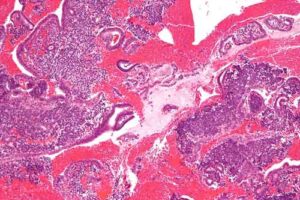

Parto dopo i 30 anni abbassa rischi del tumore dell’endometrio